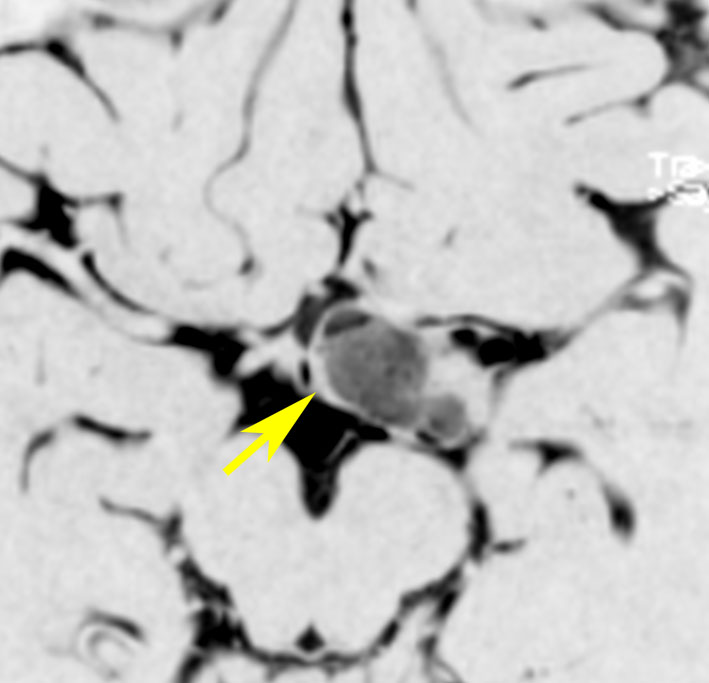

生後7カ月の幼児です。目が揺れるようになり(振り子様眼振)眼科を受診して腫瘍が発見されました。小児脳腫瘍の治療ができる病院へと紹介されました。

1ヶ月後にまたMRI検査がされました。乳児ですから検査にも麻酔が必要です。腫瘍は明らかに大きくなっています。左視神経から視索の腫瘍化が著しいので右側だけかすかに視力が残っているかもしれません。視力は明かりがわかる程度(明暗弁)と評価されました。

主治医の先生からこの赤ちゃんの両親に手術が提案されました。理由は,「とってみなければどんな腫瘍かわからない,病理診断ができないと制癌剤(化学療法)が選択できない」というものです。

こんなことを書くのは悪いことかもしれませんが,まったく馬鹿げた提案です。この画像はどこをどう見ても視路から発生した毛様粘液性星細胞腫です。画像はpathognomonic(日本語で火を見るよりも明らか)です。この小さな子に,全身麻酔をして開頭手術で生検病理診断すれば,それだけで3週間は化学療法の開始が遅れます。その間に明かりも見えなくなってしまう(完全失明する)可能性が高いでしょう。2021年時点でも,開頭手術による生検術は行われていますが,こんな重病の小さな子どもの頭を無用に開くなど,私にはもう理解不能です。

この様な増殖力が早い毛様粘液性星細胞腫は,髄液播種(脳脊髄に広範囲に転移)することがあります。手術で細胞を散らせば致命的な播種を誘発する可能性さえあります。